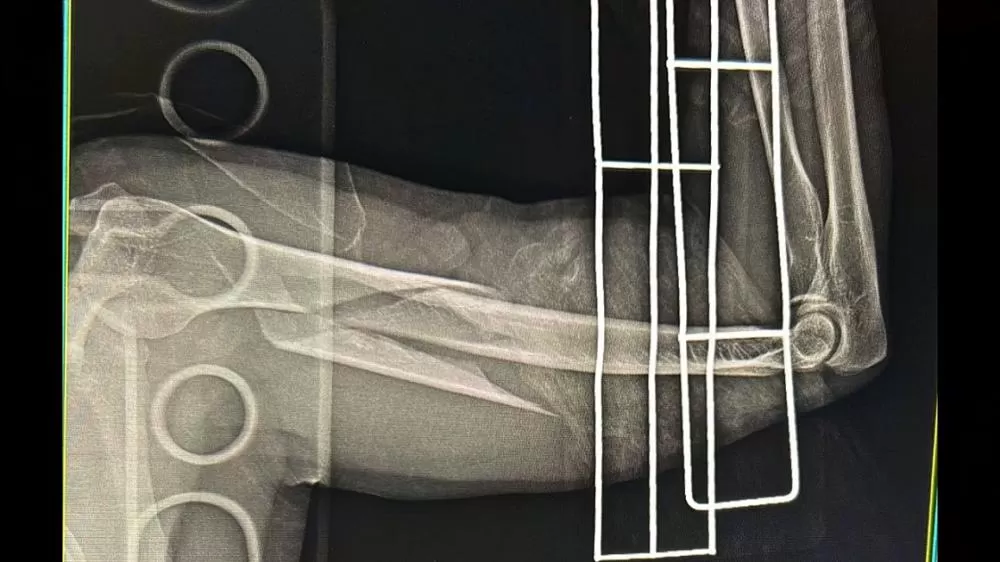

Vítima sofreu fraturas múltiplas

De acordo com informações repassadas à equipe de jornalismo, o motociclista foi identificado como Josiel. Ele sofreu fraturas nas duas pernas e em um dos braços, sendo considerado um quadro grave.